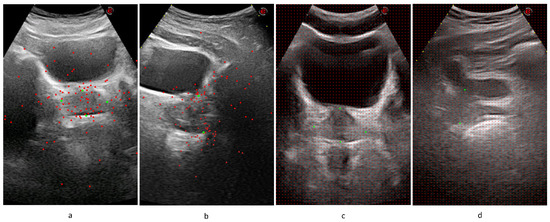

The locations of the training patches were chosen randomly from a normal distribution around diameter endpoints, while evenly spaced patches were created from test images in a sliding window manner with a stride of 10 pixels. The system extracts 200 patches from each transverse and sagittal image of the training set, which can be considered as an augmentation method that increases size of the training data set. The number of patches extracted from test images changes according to the image size. Sample training patch locations are represented on Figure 4a,b, and test patch locations are represented on Figure 4c,d.

Figure 4. Patch centers are represented on AUS images. Expert marks are shown in green, while patch centers are shown in red. (a) Random sample training patch centers on a transverse image. (b) Random sample training patch centers on a sagittal image. (c) Sample test patch centers on a transverse image. (d) Sample test patch centers on a sagittal image.